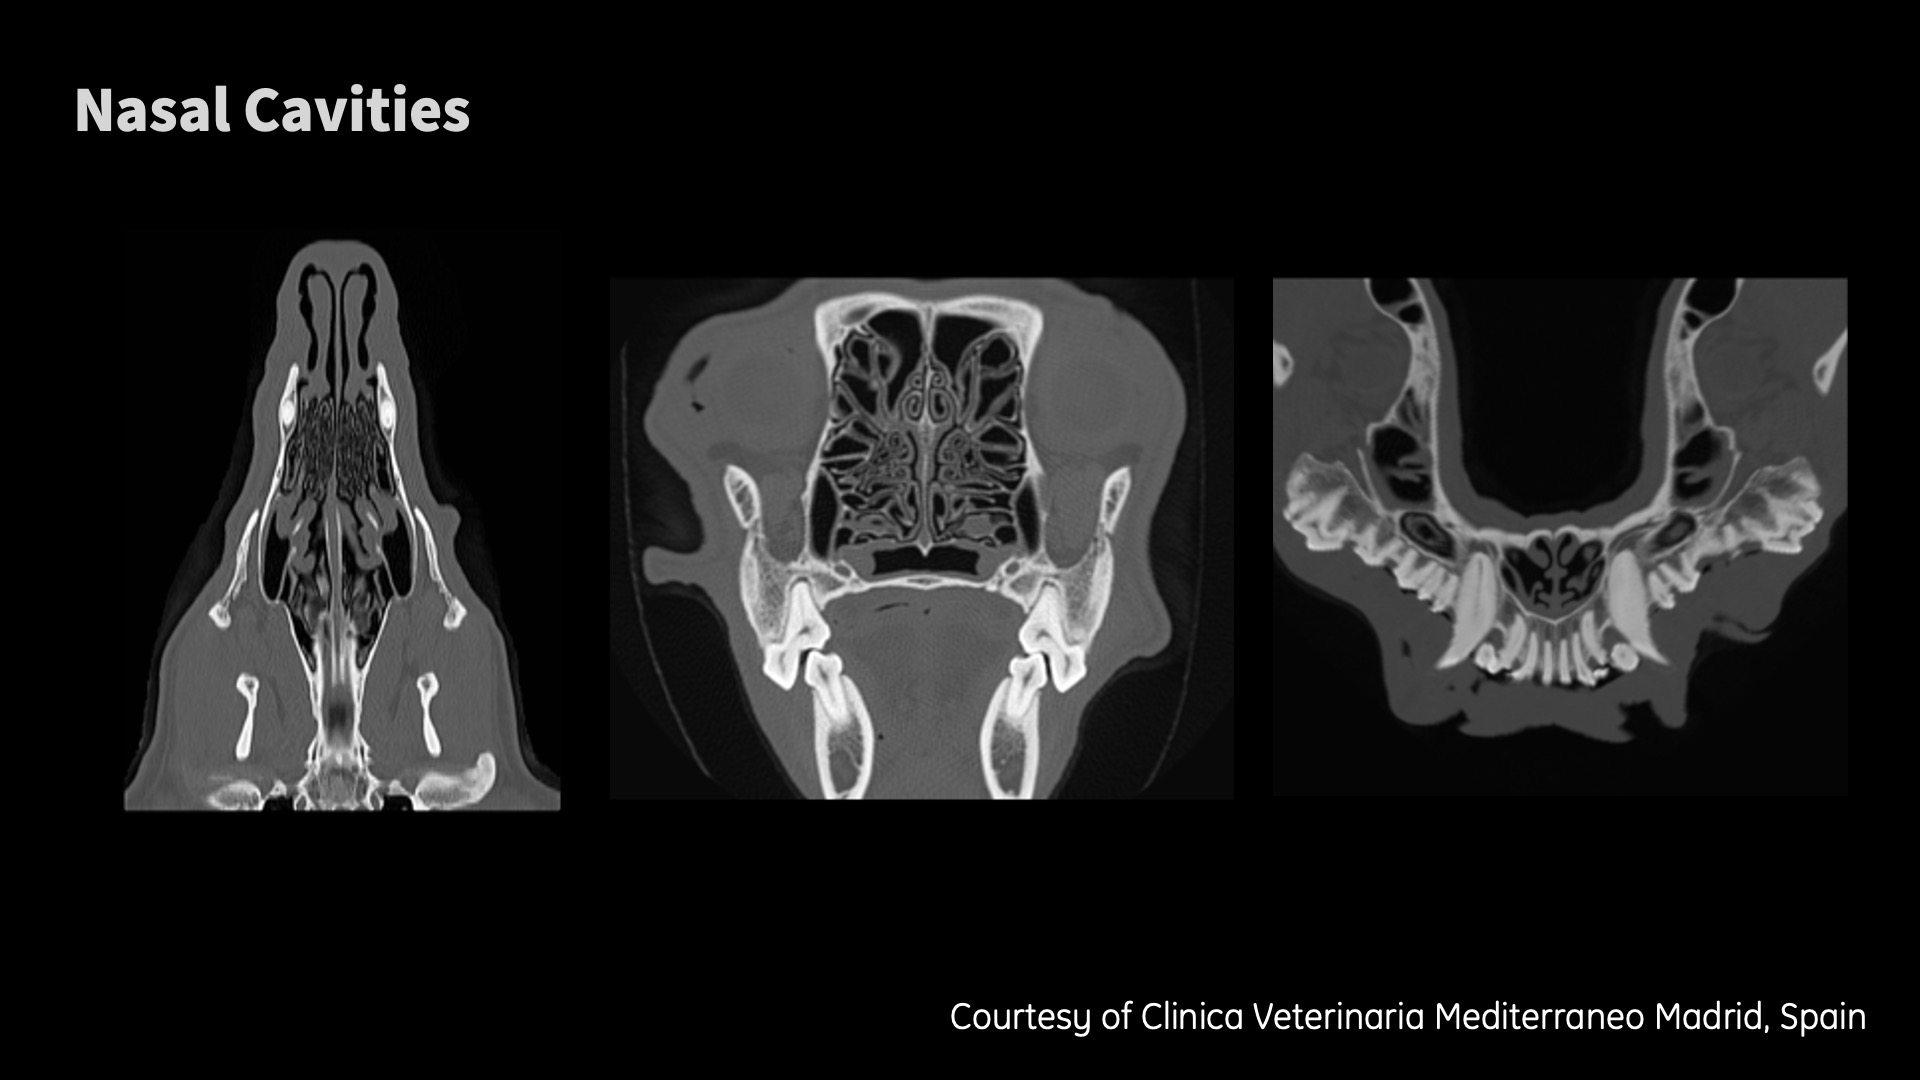

Clinical images

Don’t need to be an eagle to see the details